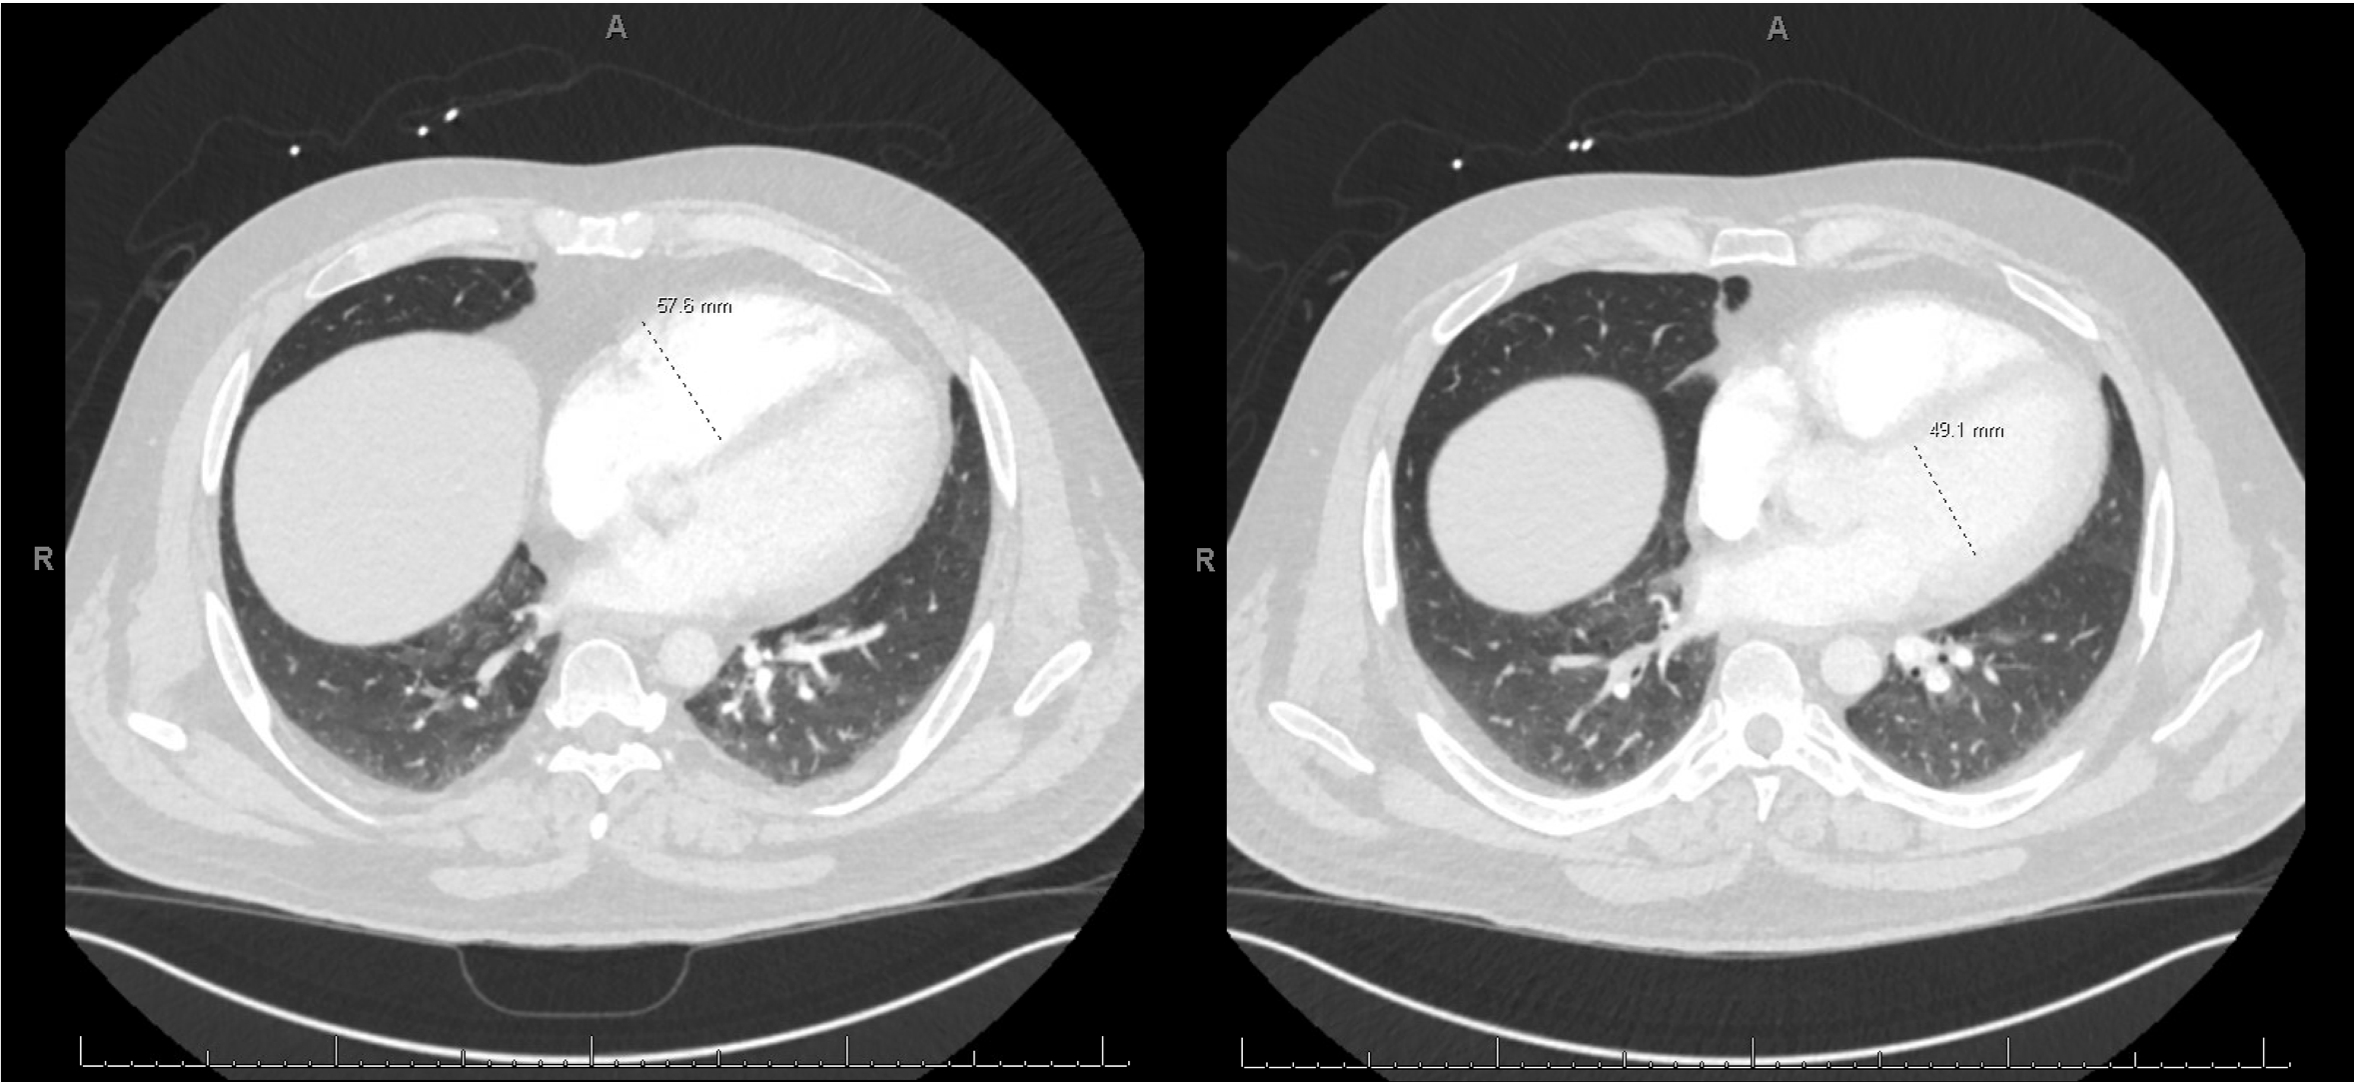

A 44-year-old male with a remote history of resected melanoma presented with acute-onset left upper extremity numbness and discoloration, progressing proximally. He also reported worsening dyspnea over one week. Physical exam revealed an absent left radial pulse and oxygen requirement of 6L via nasal cannula. CT angiography identified a left axillary artery thrombus with distal brachial artery reconstitution and bilateral pulmonary emboli. RV strain was confirmed by an RV/LV ratio of 1.2. Transthoracic echocardiogram demonstrated RV dilation and dysfunction, with a suspected PFO.